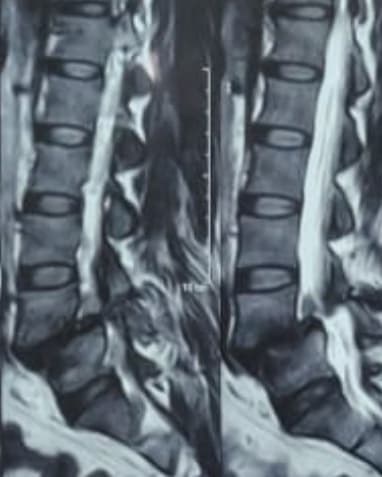

Patient History: A 42-year-old woman presented with chronic low back pain and radicular pain in both lower limbs, aggravated by standing and walking.

Investigations: MRI and dynamic X-rays of the lumbar spine revealed Grade II Lytic Anterolisthesis at L4-5.